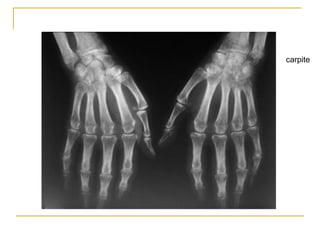

Radiographie standard :

les signes caractéristiques de la PR sont rarement visibles

avant 6 mois d’évolution

-un épaississement des parties molles,

-une augmentation de la transparence radiologique

épiphysaire, l’« ostéoporose en bande »

-érosions périarticulaires, puis

-des géodes intraosseuses juxta-articulaires caractéristiques

et secondairement

-le pincement de l’interligne articulaire

carpite